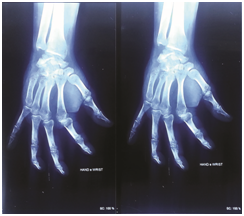

Initially treatment started with NSAID and hand elevation. On the next day hand swelling was minimally subsided, closed reduction and percutaneous k-wire fixation was done under general anaesthesia with c-arm guidance. The reduced base of fifth metacarpal bone fixed to fourth and partly third metacarpal base by passing a k-wire transiously which maintain the inter metacarpal joint. Another k-wire passing obliquely through base of fifth metacarpal to hamate, it give stability of hamato-metacarpal joint.

Per-operative radiographs ensure the base of fifth metacarpal placed in position. Clinically there was no depression on dorsomedial aspect of proximal position of Right carpus and little finger deformity was corrected. All finger joints moves freely. Proper dressing of k-wire entering points done. Finally apply cock-up slab for immobilization of wrist joint and metacarpal bones. Post-operative x-ray ensure the base of fifth metacarpal and both k-wires in position.

Figure 2 Postoperative Radiographic view of AP and Oblique.